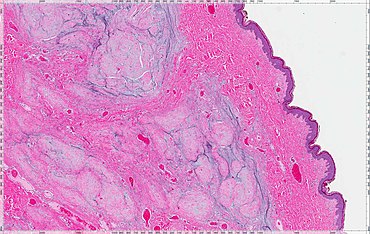

A cutaneous myxoma, or superficial angiomyxoma, consists of a multilobulated myxoid mass containing stellate or spindled fibroblasts with pools of mucin forming cleft-like spaces. There is often a proliferation of blood vessels and an inflammatory infiltrate. Staining is positive for vimentin, negative for cytokeratin and desmin, and variable for CD34, Factor VIIIa, SMA, MSA and S-100.[1]